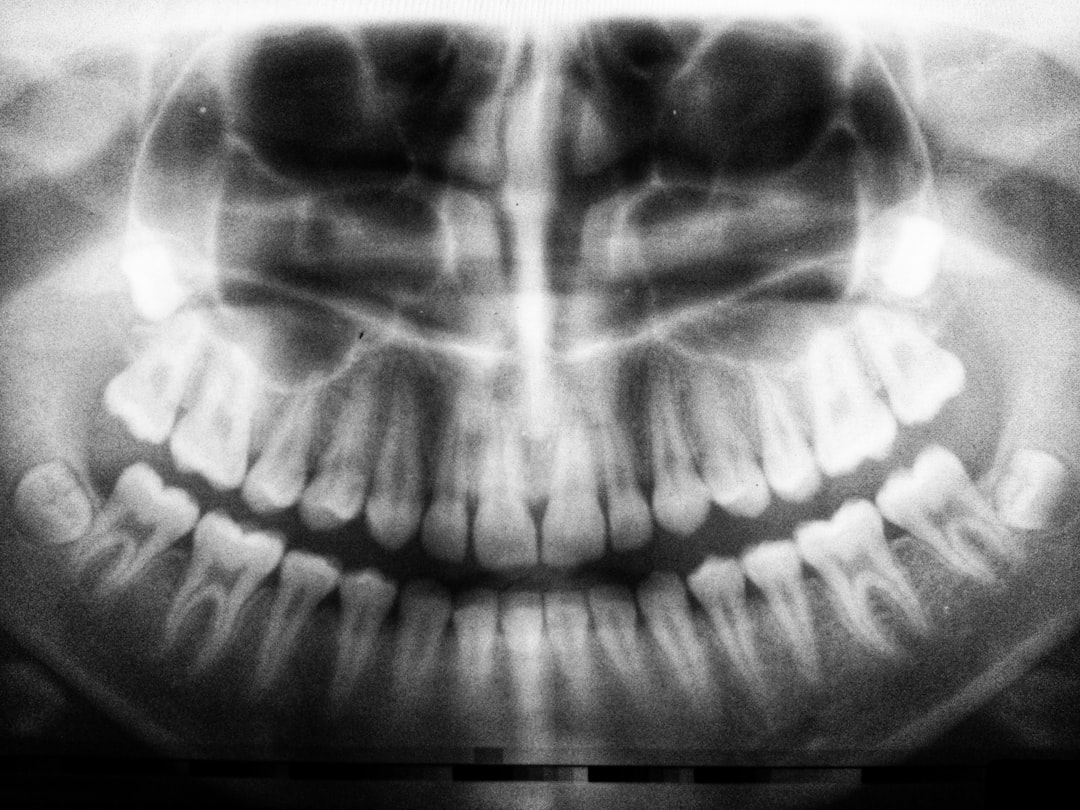

임플란트 치료는 그야말로 혁신적인 과정입니다. 이를 통해 실신의 자연스러움을 회복할 수 있으며, 생활의 질을 높여주는 여러 장점이 있습니다. 임플란트 치료를 받은 많은 사용자들이 복잡한 치료 과정을 거쳐 얻은 긍정적인 변화를 생생히 전하고 있습니다. 이들이 남긴 임플란트 지원금 후기에서도 그런 긍정적인 태도를 확인할 수 있습니다.

임플란트는 자연치아에 대한 대안으로서 그 기능 및 외형이 뛰어나 많은 사람들이 선택하고 있습니다. 자연스러운 외관과 더불어 저작력이 뛰어나 실제 음식 섭취 시 큰 도움을 줍니다. 또 다른 사용자도 “이제는 무엇이든 자유롭게 먹을 수 있어 좋다”며, 그동안의 걱정이 한순간에 사라졌다고 경험을 전했습니다.

아울러, 임플란트는 주변 치아에 피해를 줄 염려가 적어 장기적으로 건강을 유지하는 데 도움이 됩니다. 그로 인해, 다양한 사회적 활동에 참여하고, 자신감을 가지고 생활할 수 있는 계기가 마련되기도 합니다. 이런 면에서, 임플란트 치료는 단순히 치아의 문제를 덮는 것이 아니라 생활전반에 긍정적인 영향을 미친다는 사실을 강조할 수 있습니다.